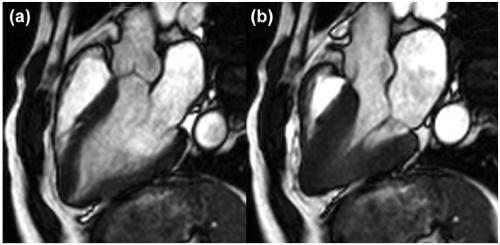

4. MRI:

表现心尖部位的心肌肥厚,舒张期末见心尖部黑桃样改变,收缩期末见心尖腔完全消失。

左(a)舒张期;右(b)收缩期